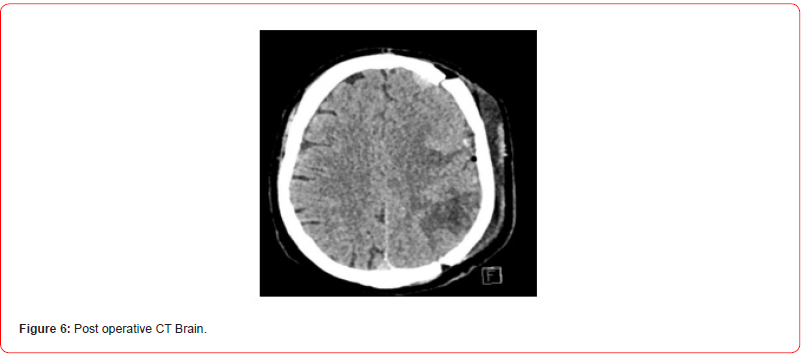

Clinical and radiological diagnosis of en-plaque meningioma of left frontoparietal convexity compressing the underlying parenchyma was made. Patient was planned for craniotomy and surgical excision of lesion. Intraoperatively after removing the calvarium at left fronto -parietal aspect. Dura was visible with some nodular lesions underneath it. On opening the dura we found three lesions lying over cortical surface of parietal and frontal lobes, yellowish nodular oval shaped well defined lesions attached with dura with no clear demarcation/plane of dissection between lesion and brain tissue. Suspecting some high grade lesion en mass excision was done except the part of nodule present over middle frontal gyrus which was in proximity of pial vessel to avoid pial violation. Tissue sample was sent for histopathological examination. On post operative day 3 patient had an episode of focal seizure in right hand. CT brain was done which showed patchy edema in the subcortical white matter in the left parietal lobe , involving the postcentral gyrus and to a lesser extent the left frontal lobes with few foci of hemorrhage. No increase in mass-effect since preoperative study. No significant midline shift or brainstem herniations (Figure 6).